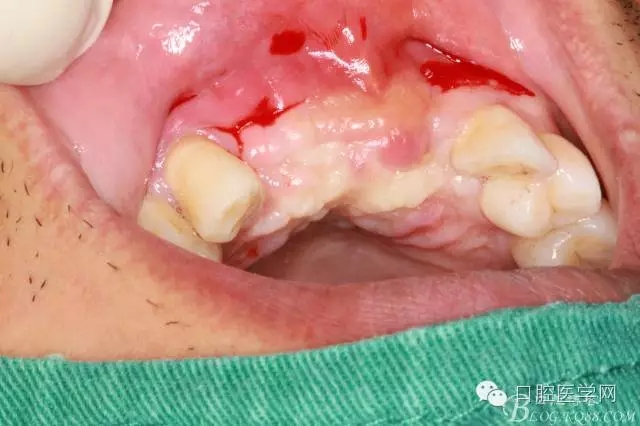

為他院轉(zhuǎn)診患者。男,無(wú)吸煙史,前牙因齲壞治療后,外力折斷導(dǎo)致拔除?,F(xiàn)拔除該牙后兩個(gè)多月。 左上區(qū)域骨寬度不足,計(jì)劃植入種植體同期GBR。

左上區(qū)域骨寬度不足,計(jì)劃植入種植體同期GBR。

遺憾沒有保留術(shù)前口內(nèi)照片,只有術(shù)后的。